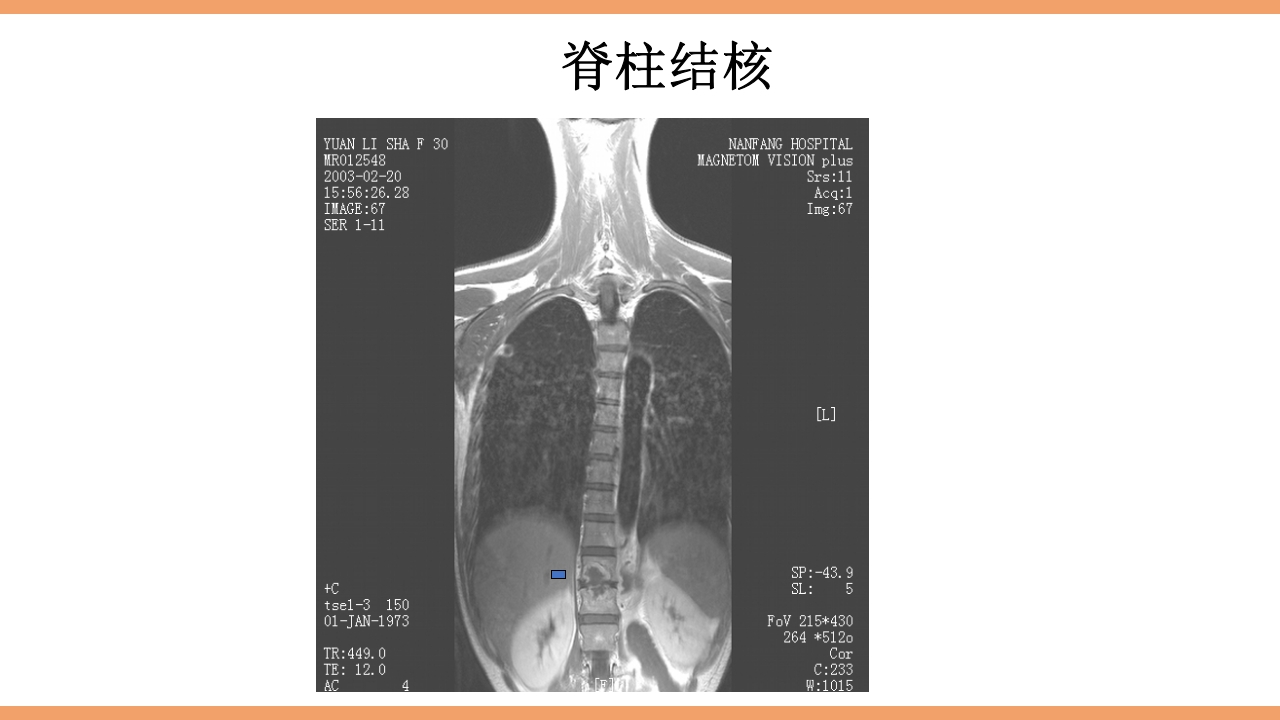

CONTENTS 目 录 1 结核简介 2 脊柱结核概论 3 病灶形成和发展 4 解剖位置 5 病理病因 6 分型 7 临床表现及症状体征 8 影像学及实验室检查 9 治疗 10 护理 11 治愈标准 12 出院指导 西医谓之为: 骨、关节结核:结核病菌侵入骨或关节内并在其中繁殖,出现 一系列的病理改变。 中医谓之为: 骨痨:由于结核杆菌侵入骨或关节而引起的化脓性病变,其病 发于骨,消耗气血津液,导致形体虚赢,缠绵难愈故其名为骨痨。 成脓破溃后,脓液中伴败絮状痰样物,可流窜他处形成寒性脓肿, 又名流痰。骨痨发于脊柱称之为脊柱痨、龟背痰。 胸椎结核为龟背痰,腰椎结核为肾俞虚 痰,骶尾椎结核为尾闾发。 1.脊柱结核是一种继发性病 变,约90%继发于肺结核.少 数继发于消化道结核、胸膜 结核或...